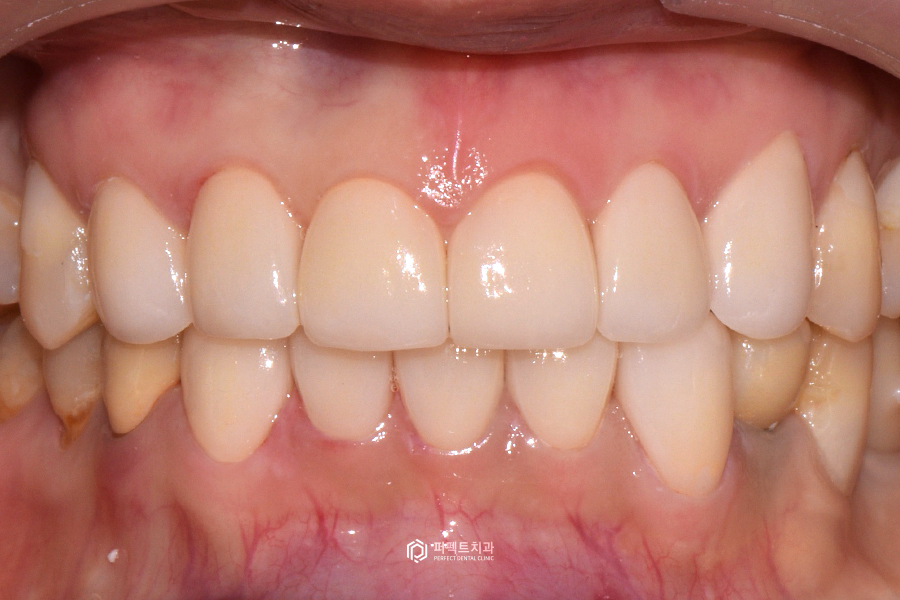

초진 사진에서 보신 것처럼 변색된 부분과 삼각형 형태의 치아모양을 개선해서 반듯하고 예쁘게 완성을 해드렸습니다. 아래 치아도 빈 공간(블랙트라이앵글) 없이 완성이 되었고, 치아색상의 경우 자연스러운 치아를 원하셔서 많이 밝게 해드리지 않고 직접 고르신 색상으로 진행을 하였습니다.

또한 치아 형태도 여성스러운 느낌을 원하신다는 의견을 반영하여 라인앵글이라고 하는 끝 부분을 살짝 둥글게 디자인 하였습니다.

얼룩덜룩하고 마모된 치아는 치아만 보았을 때 나이가 들어보이는 느낌이 드는데, 깔끔한 치아는 20대 치아 같은 느낌이 들 수 있습니다.